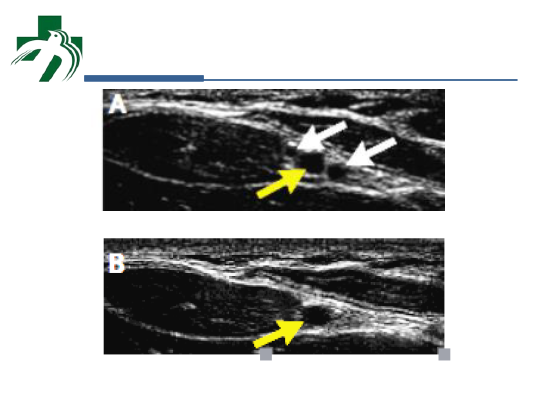

PiCCO是临床上常用的一种血流动力学监测技术。本课程介绍了PiCCO脉搏波形轮廓分析和经肺热稀释两种方法测量心输出量的原理,PiCCO在临床应用中的优势和局限性,如何使用PiCCO常用参数指导临床治疗,以及实际操作中的技巧和注意事项。最后简要复习了超声引导下动脉穿刺置管的技巧。